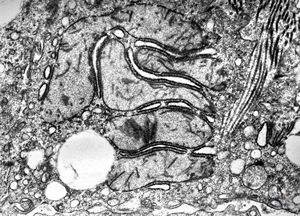

F,1y. | mitochondrial changes - Reye hepatocerebral syndrome

M,5y. | mitochondrial changes - Reye hepatocerebral syndrome